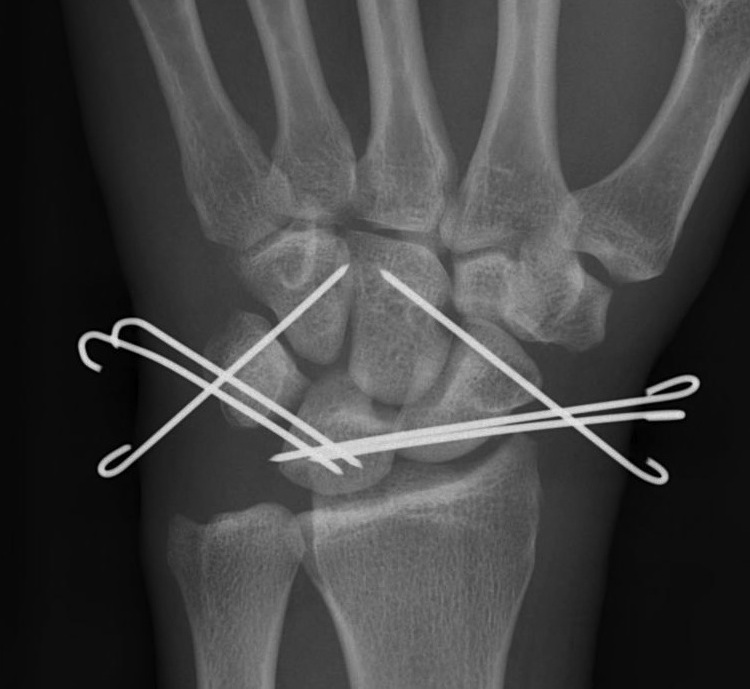

2. Lunate dislocation

Lunate dislocates / usually volar

Carpus remain aligned with distal radius

Perilunate dislocation / No scaphoid fracture

Technique

Dorsal approach

- K wire joysticks in scaphoid and lunate and reduce

- K wires scaphocapitate / scapholunate / lunatetriquetral (areas of ligament rupture)